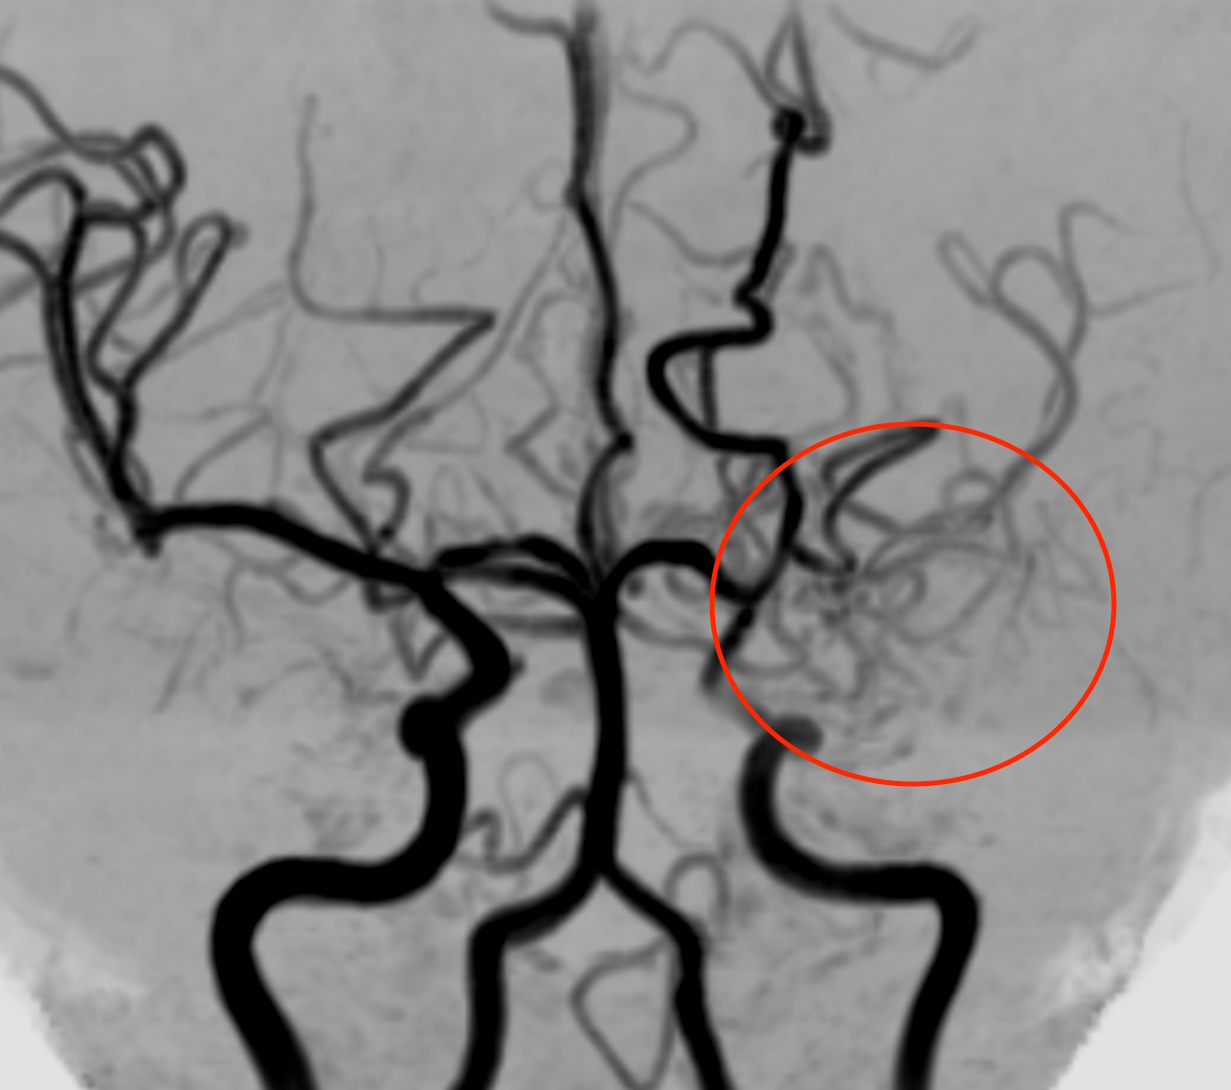

※下は他のもやもや病の方の画像で、左側の内頚動脈が途中でふさがっています。

左もやもや血管

このように血管がつまって血流が悪くなった場合に、足りない血液を補おうとして毛細血管が発達してもやもやと見えるため、「もやもや病」と名付けられました。若い方の脳梗塞や脳出血の原因となります。遺伝子が特定されていますが、必ずしも全員が発病するわけではありません。